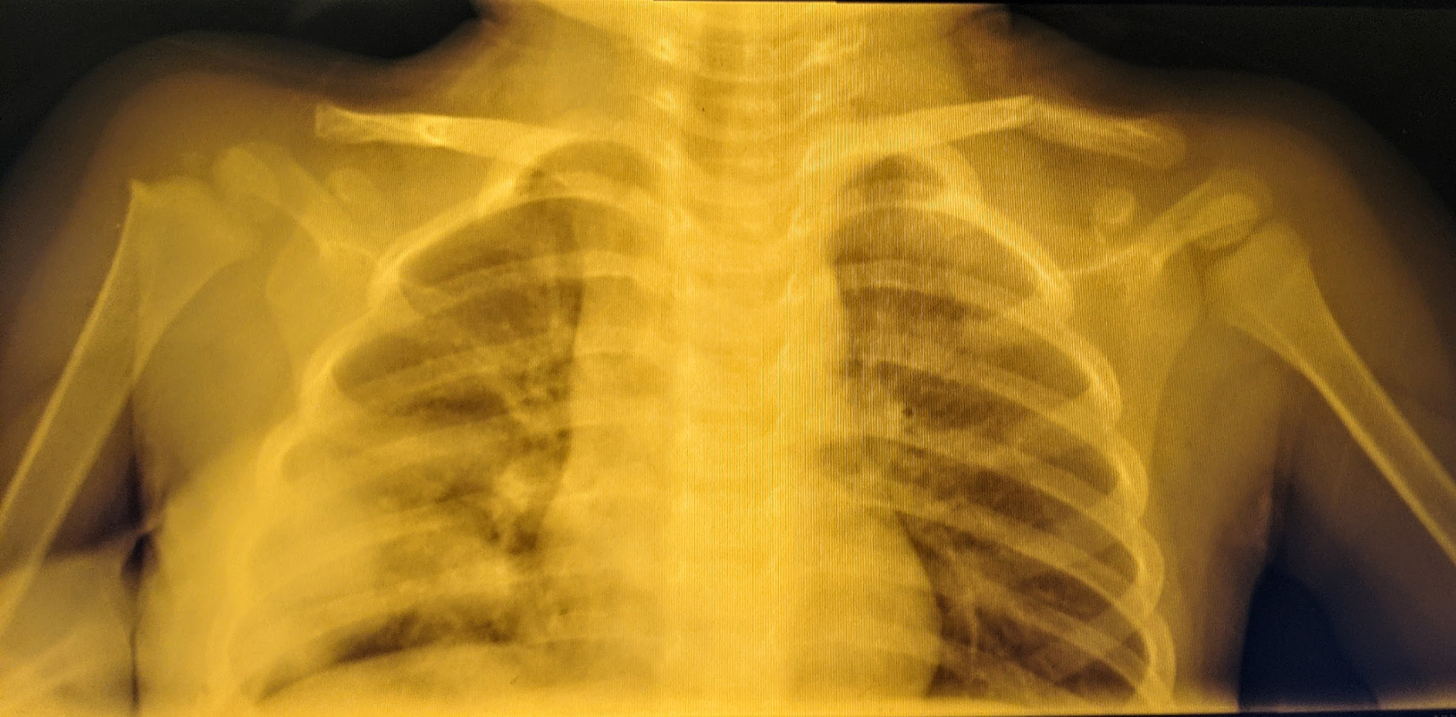

Last Sunday, only a few hours after I sent out my newsletter, my son fell and broke his collarbone. The doctor walked me through the X-ray reassuring me that this was a very common fracture among kids. But something bothered me deep down. There was a broken bone inside my boy and I knew nothing about bones or how they heal.